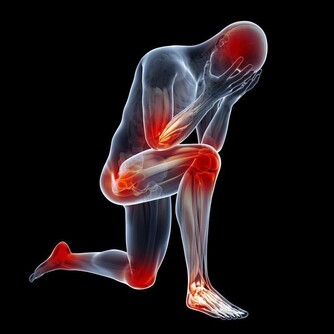

當膀胱癌到達第4階段時,原始腫瘤經常生長並推動膀胱壁。癌細胞可能已經擴散到靠近膀胱的器官或更遠的器官,例如肝臟或肺部。於是其症狀可能包括:

1、疲倦或虛弱;

2、小便時疼痛;

3、排尿困難或無法排尿;

4、身體一側的下背部疼痛;

5、體重減輕;

6、腳部腫脹;

7、骨痛。